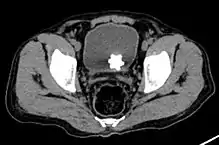

Diagnosis

The diagnosis of bladder stone includes urinalysis, ultrasonography, x rays or cystoscopy (inserting a small thin camera into the urethra and viewing the bladder). The intravenous pyelogram can also be used to assess the presence of kidney stones. This test involves injecting a radiocontrast agent which is passed into the urinary system. X-ray images are then obtained every few minutes to determine if there is any obstruction to the contrast as it is excreted into the bladder. Today, intravenous pyelogram has been replaced at many health centers by CT scans. CT scans are more sensitive and can identify very small stones not seen by other tests.[8]

Jackstone calculus

Jackstone calculi are rare bladder stones that have an appearance resembling toy jacks. They are almost always composed of calcium oxalate dihydrate and consist of a dense central core and radiating spicules. They are typically light brown with dark patches and are usually formed in the urinary bladder and rarely in the upper urinary tract. Their appearance on plain radiographs and computed tomography in human patients is usually easily recognizable. Jackstones often must be removed via cystolithotomy.[10]